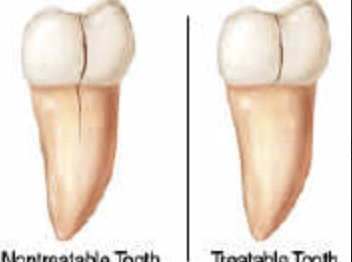

Diente fisurado, no tratable

Diente fisurado tratable

Fractura cuspídea tratable